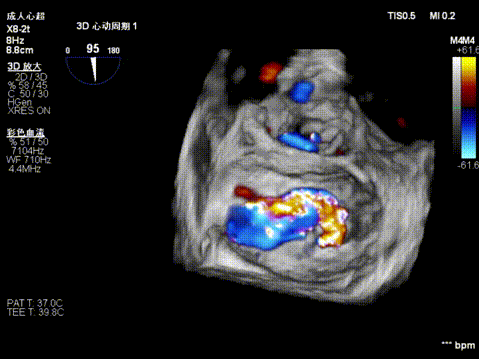

3D enface view示二尖瓣P2P3区瓣叶脱垂,偏心性返流

3D测量二尖瓣瓣口面积4.50cm² 病变宽度为1.79cm